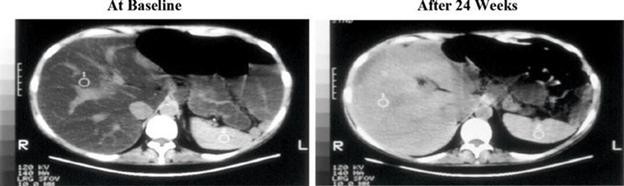

Steatosis:

Upon conversion of the quantification of computed tomography, or CT, values to magnetic resonance imaging proton density fat fraction, or MRI-PDFF, significant differences in the least square, or LS, mean change from baseline in estimated MRI-PDFF were observed in the IV Choline Chloride group in comparison to placebo group at Week 4 through Week 24, demonstrating a clinically meaningful and statistically significant reduction in steatosis. When LS mean percent changes from baseline in MRI-PDFF were compared between treatment groups, significant differences in LS mean changes (range, 31.7% to 53.6%) were observed from Weeks 4 to 24 with p-values of 0.0009 to 0.0297 favoring the IV Choline Chloride group.

Figure 3. Liver CT Images: Before and After Treatment with IV Choline Chloride